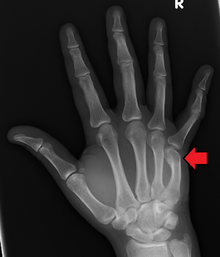

DP (PA) right hand x-ray showing fracture at the neck of fourth metacarpal bone | |

Boxer's Fracture is a colloquial term for a fracture of one of the metacarpal bones of the hand. Classically, the fracture occurs transversely across the neck of the bone, after the patient strikes an object with a closed fist. Alternate terms include scrapper's fracture or bar room fracture.